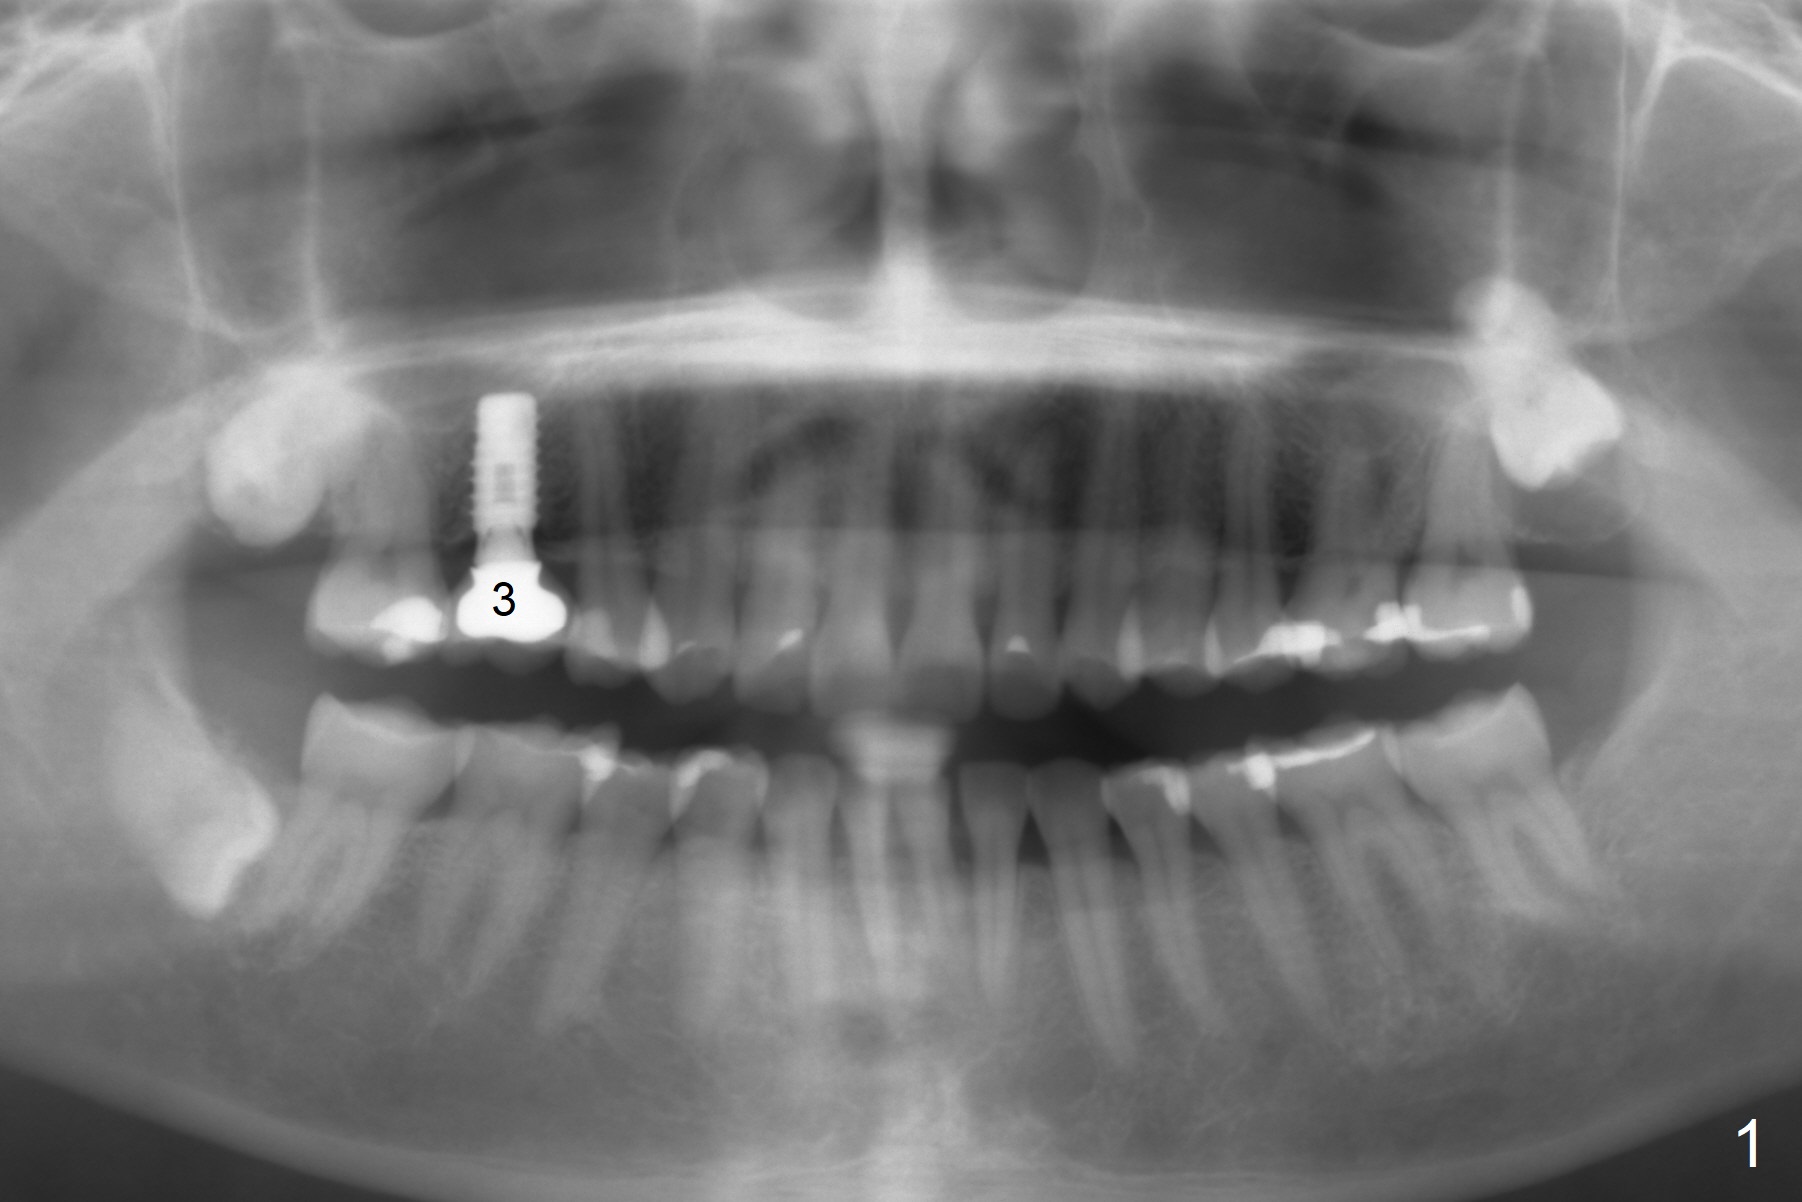

A 55-year-old woman has an implant at #3 (Fig.1). There has been swelling and periapical radiolucency associated with #14 for > 6 months (Fig.2). Finally a mesiodistal crack is found. If infection with bone loss is too severe, socket preservation will be performed. The depth of initial osteotomy in the septum will be 10 mm (Fig.3). Try not to perforate sinus floor. Place an IBS implant as large as possible. If the infection is moderate, use IS one.